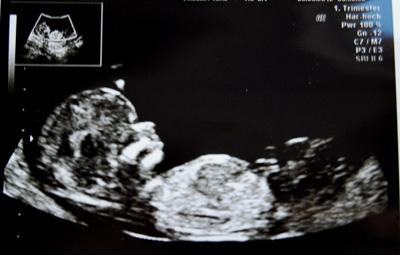

Hallo, und nein, ich bin nicht 15, aber ich wollte so gerne Blümchen sein und hab einfach wild eine Zahl dahinter getippt, weil Blümchen allein natürlich schon belegt war! Ich bin 27, habe bereits 2 wundervolle Töchter (22 Monate und 5 1/2 Jahre) und erwarte nun unser 3. Kind, welches sich trotz geplanter Steri nochmal eben schnell eingeschlichen hat! Nach anfänglichem Schock freue ich mich nun doch sehr auf unser 3. Wunder. Berechneter ET ist der 17.09. und ich bin jetzt in der 13. Woche. Ich hatte bereits 2 Konisationen (Op´s am Gebärmutterhals) und bin deshalb schon seit Beginn der Schwangerschaft mit Beschäftigungsverbot zu Hause. Darf zwar alles machen (bis jetzt), soll mich aber schonen. Nach einer Sturzblutung und Klinikaufenthalt in der 9. Woche weiß ich auch, dass schonen wirklich schonen heißt. :-) Zum Glück ist alles gut gegangen. Heute war große VU und NT-Messung. Nackenfalte liegt bei 0,7mm und ist somit fast besser als gut! *freu* Außerdem ist das Baby bereits der 14. Ssw nach entwickelt, also ein paar Tage weiter. ET bleibt jedoch der "alte". Und noch eine Überraschung gab es: Die Ärztin konnte unserem Krümel direkt zwischen die Beinchen schauen und meinte, dass man bei einem Bub durchaus schon etwas erkennen könnte. Da sie aber nichts sah, geht sie stark davon aus, dass wir unsere 3. Zicke erwarten! (Mein armer Mann :-) ). Mal sehen, ob es sich das nächste mal bestätigt, darauf verlassen tue ich mich nun erst mal nicht.. So, entschuldigt, jetzt ist aus der kurzen Vorstellung doch ein ziemlich langer Text geworden.. Lg Blümchen

Bild zu Mag mich auch zu Euch gesellen - Forum für September - Mamis

Herzlich Willkommen im September-Bus und eine gute Fahrt. Deine Schwangerschaft hat ja turbulent begonnen... Ich hoffe, nun kehrt etwas Ruhe ein, aber vermutlich halten Dich Deine zwei Kids auch ordentlich auf Trab. Schönes Ultraschallbild übrigens! Es ist einfach unglaublich, dass da schon so ein richtiges kleines Menschlein zu sehen ist, obwohl man erst 13. SSW ist. LG